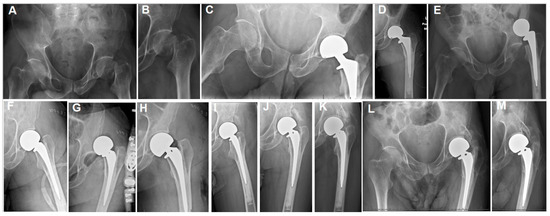

| Case | Age | CP Type | Implant Type | Complications | Outcome |

|---|---|---|---|---|---|

| 1 | 71 | Ataxic | Cemented bipolar | HO grade 4 | |

| 2 | 55 | Quadriparitic | Cemented bipolar | Dislocation and early revision due to stem loosening. Recurrent dislocation managed with closed reduction and bracing. | Ho grade 3 |

| 3 | 68 | Ataxic | Cementless unipolar | HO grade 4 | |

| 4 | 60 | Unidentified | Cemented bipolar | HO grade 2 | |

| 5 | 33 | Contralateral spastic hemiplegic | Cemented bipolar | HO grade 3 | |

| 6 | 47 | Ipsilateral spastic hemiplegic | Cementless bipolar | Acetabular protrusion, wheelchair bound | HO grade 4 |